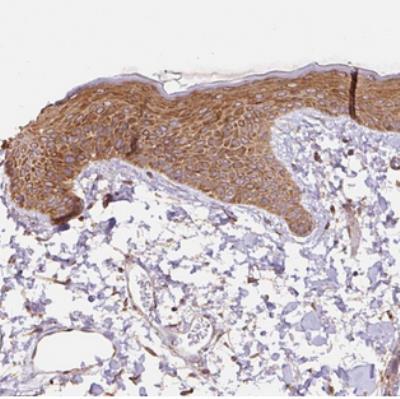

- Immunohistochemistry: COX8A Antibody [NBP2-30764] - Staining of human skin shows strong cytoplasmic positivity in keratinocytes.